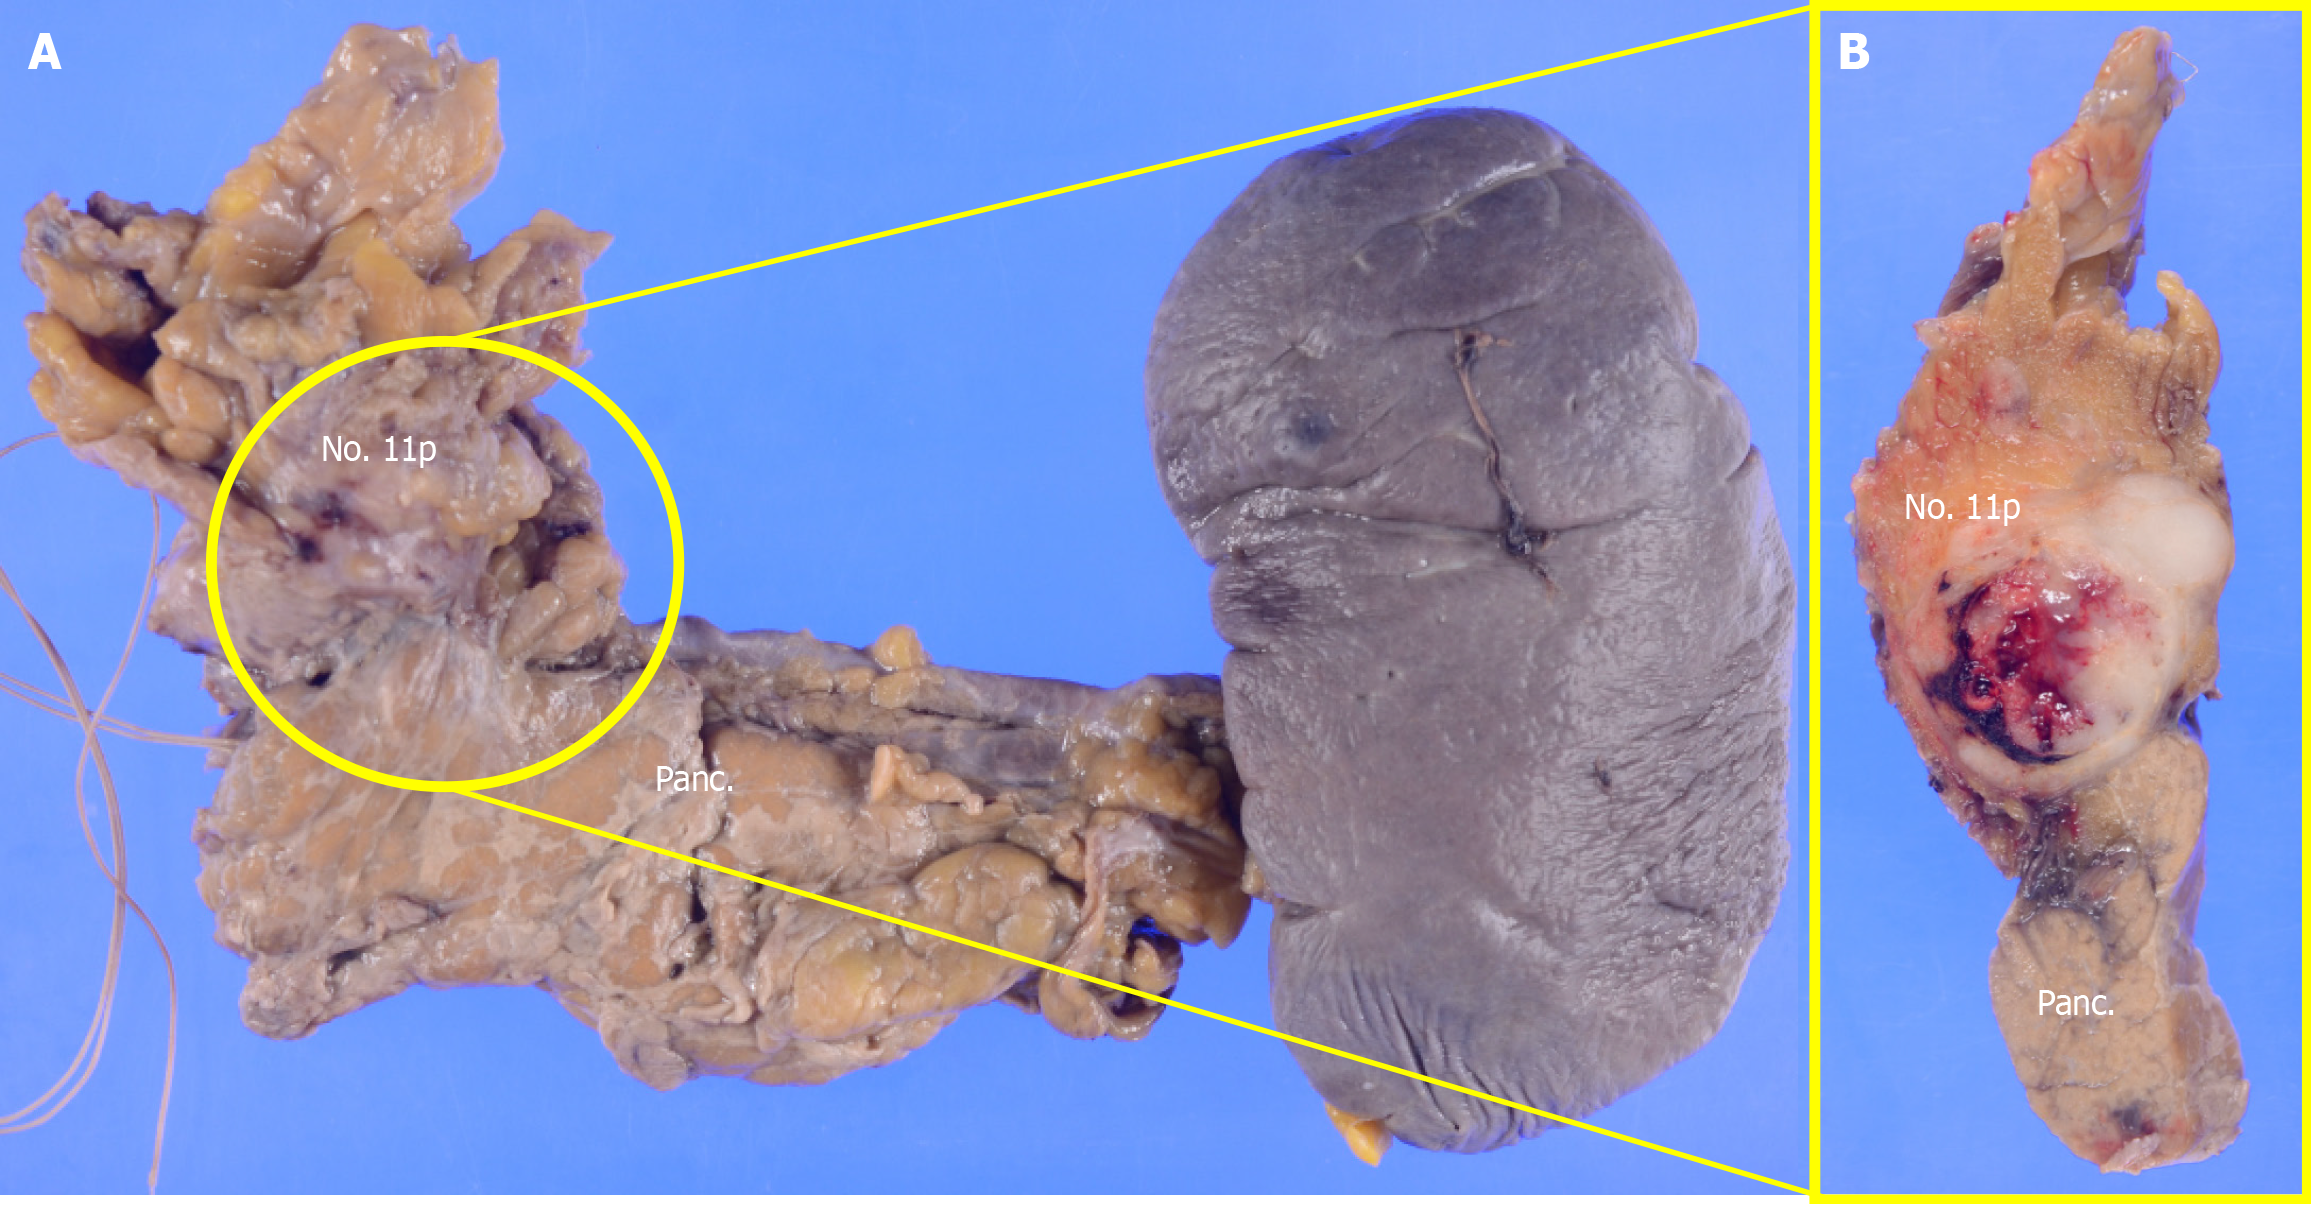

The postoperative pathological diagnosis was NEC, type 5, ypT4aN4 (No. 108, No. 11p) M0 ypStage IVa[10,11]. The resected pancreatic body and spleen showed that the No. 11p lymph node was macroscopically attached to the pancreas. However, pathological examination confirmed the absence of direct infiltration (Figure 4). Histopathological examination of the primary lesion revealed that while multinucleated giant cells and pleomorphic cells were present in the primary lesion, SCC detected before chemotherapy was not observed. Instead, large cell-type NEC was detected. Large pleomorphic cells with a high nucleus-to-cytoplasm ratio formed solid nests and proliferated (Figure 5A-E). Ki-67 staining was positive in more than 90% of the cells. Immunohistochemical staining revealed CD56 (+), chromogranin A